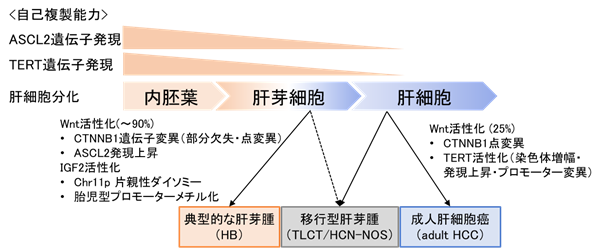

小児肝がん(肝芽腫)の発生機序を解明

日本小児肝癌スタディグループで行ってきた全国多施設共同臨床試験JPLT-2試験に登録され治療された小児肝腫瘍のうち同意を...